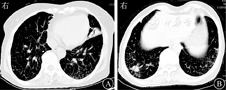

患者女,68岁,农民,2月前因"反复发热、咳嗽咳痰伴咽痛、乏力"入住当地医院。患者2017年9月起无明显诱因下出现间歇性发热,低热为主,具体体温不详,以下午及傍晚明显,伴咳嗽,咳黄色(后转白色)黏痰,伴全身乏力、咽痛、颈前区疼痛、恶心、心慌胸闷,无呕吐,无鼻塞流涕,无腹痛、腹胀、腹泻,无胸痛烧心,无畏寒怕热,无盗汗消瘦,无四肢麻木等。诊断为弥漫性毒性甲状腺肿(Graves病),予泼尼松、美托洛尔等药物治疗2周后症状曾好转。后颈前区疼痛及发热乏力咳嗽等症状加剧,查肺部CT提示两肺散在多发结节,支气管炎,右肺中叶及左肺上叶下舌段支气管扩张,伴炎症机化。实验室检查:红细胞沉降率31 mm/1 h,C反应蛋白1.5 mg/L。诊断为:①Graves病;②肺部感染原因待查。11月6日转入浙江大学医学院附属第一医院进一步治疗。体格检查:体温37.7℃,脉搏110次/min,呼吸20次/ min,血压111/64 mmHg(1 mmHg=0.133 kPa)。患者神志清,精神可,双肺呼吸音粗,未闻及明显干湿啰音,心律尚齐,心率快,未闻及病理性杂音,腹软,无压痛、反跳痛,肝、脾肋下未及,肠鸣音6次/min,移动性浊音阴性,双下肢轻度凹陷性水肿,神经系统检查阴性。实验室检查:白细胞计数5.9×109/L,中性粒细胞比例0. 636,Hb 97 g/L,血小板计数159×109/L;C反应蛋白9.30 mg/L;降钙素原0.02 μg/L;肝肾功能、肿瘤标志物等正常。2017年11月10日肺部CT平扫提示:两肺多发感染性病变,两肺多发结节(图1)。入院后每天午后及傍晚有低热,体温波动于37.3~38.8 ℃,先后予左氧氟沙星、莫西沙星、头孢他啶等经验性抗感染治疗,体温仍反复波动,抗感染效果较差,怀疑肺结核可能,查结核菌素试验及结核感染T淋巴细胞斑点试验阴性;支气管肺泡灌洗液(bronchoalveolar lavage fluid,BALF)及毛刷涂片找抗酸杆菌均为阴性。2017年11月30日肺穿刺活组织检查提示:右下肺肉芽肿性炎伴坏死,抗酸阴性,痰培养抗酸杆菌2次均阴性。2017年11月28日全院多学科综合协作(multi-disciplinary team,MDT)讨论认为:肺部感染性病变首先考虑,病原体尚不明确,需考虑非结核分枝杆菌感染。继续送痰培养,后连续3次均有非结核分枝杆菌生长,菌种鉴定为鸟-胞内分枝杆菌复合群(Mycobacterium avium Complex,MAC),予利福平0.45 g+乙胺丁醇0.75 g+阿奇霉素0.5 g+莫西沙星0.4 g,1次/d联合抗感染治疗2周后,体温正常,症状基本消失,复查C反应蛋白、血常规、红细胞沉降率等基本正常,2018年2月7日肺部CT提示:病灶较前稍有吸收(图2)。出院后继续口服上述药物治疗,现已随访4个月余,病情稳定,仍继续随访中。